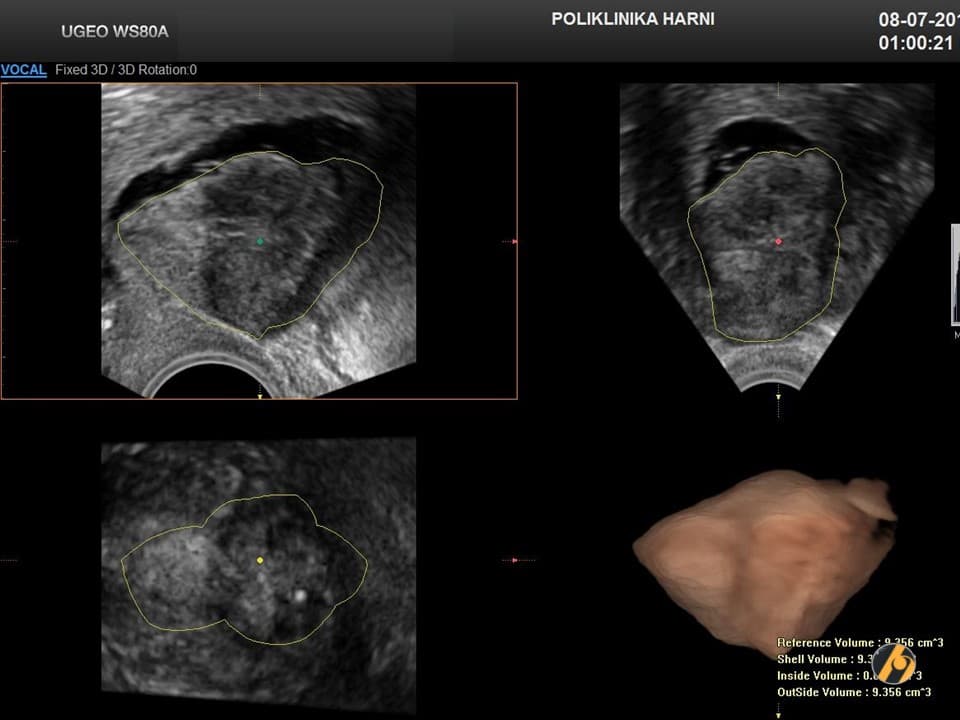

Dijagnoza

Dijagnoza mioma postavlja se temeljem anamnestičkih podataka, ginekološkog i ultrazvučnog pregleda. Ponekada su, osobito kod gigantskih mioma nužne dopunske metode kao što su intravenska urografija, CT ili MRI zdjelice, kako bi se u planiranju operativnog zahvata mogao procijeniti utjecaj mioma na okolne organe, a time i rizik povrede tih organa tijekom operacije.

Dijagnoza se postavlja ginekološkim pregledom i slikovnim pretragama.